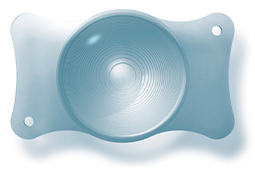

- Preserflo MicroShunt verzus trabekulektómia: klinické výsledky 6-mesačnej retrospektívnej štúdie